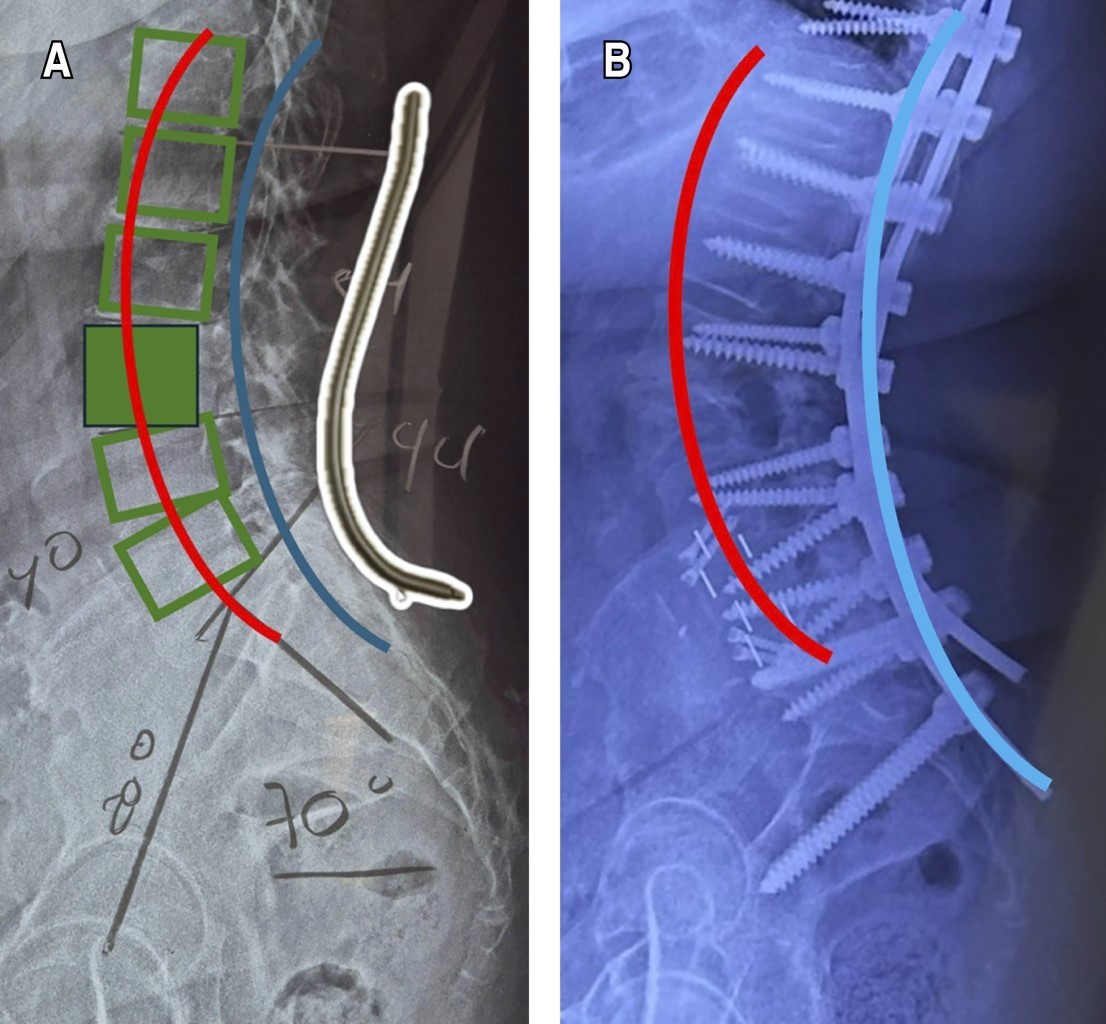

Figure 2